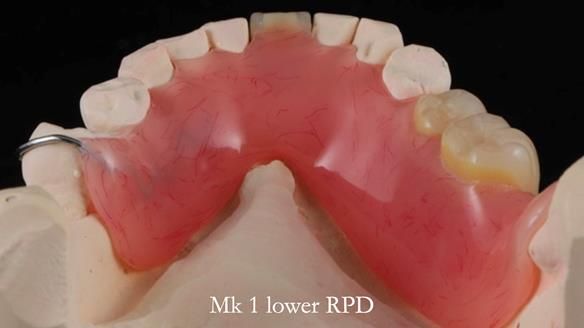

Welcome to my Newsletter 54 showing the making and fitting of dentures (a complete upper metal reinforced denture, a lower immediate partial denture and a definitive Scandinavian designed, metal based lower partial denture) for David, a 75 -year-old man. The full protocol workflow is presented including the use of dentate photographs to mimic his natural teeth.

The clinical situation and treatment process is shown in detail below. I provided the clinical work. Rowan Garstang, my dental technician, provided the technical work.

Interestingly we found that the upper complete denture when finished and fitted didn’t have good enough retention for David’s satisfaction. It was relined by adding compound to the buccal flanges – to almost overextend into the sulcus to ‘create’ a sulcus, followed by using a light bodied silicone impression material. This improved the function of the C/-considerably. A lower Scandinavian hygienically designed lower RPD was also provided which helped with occlusal stability and reseating the upper denture – further improving the fit.